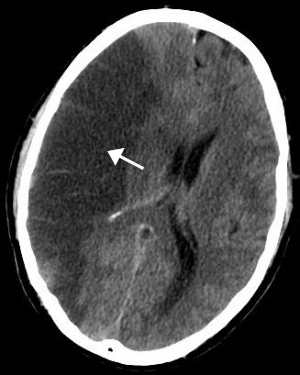

허혈성 뇌졸중으로 가장 흔한 유형의 뇌졸중입니다. 뇌의 혈관이 좁아지거나 막혀 혈류(허혈)가 심하게 감소할 때 발생합니다. 혈관이 막히거나 좁아지는 것은 혈류를 통해 이동하고 뇌의 혈관에 남아 있는 혈관에 축적되는 지방 침착물, 혈전 또는 기타 이물질로 인해 발생합니다.

경부혈전증은 경동맥 경화증은 시간이 지남에 따라 경화되어 콜레스테롤이 혈관에 축적되어 동맥의 원활한 흐름을 차단할 수 있습니다.